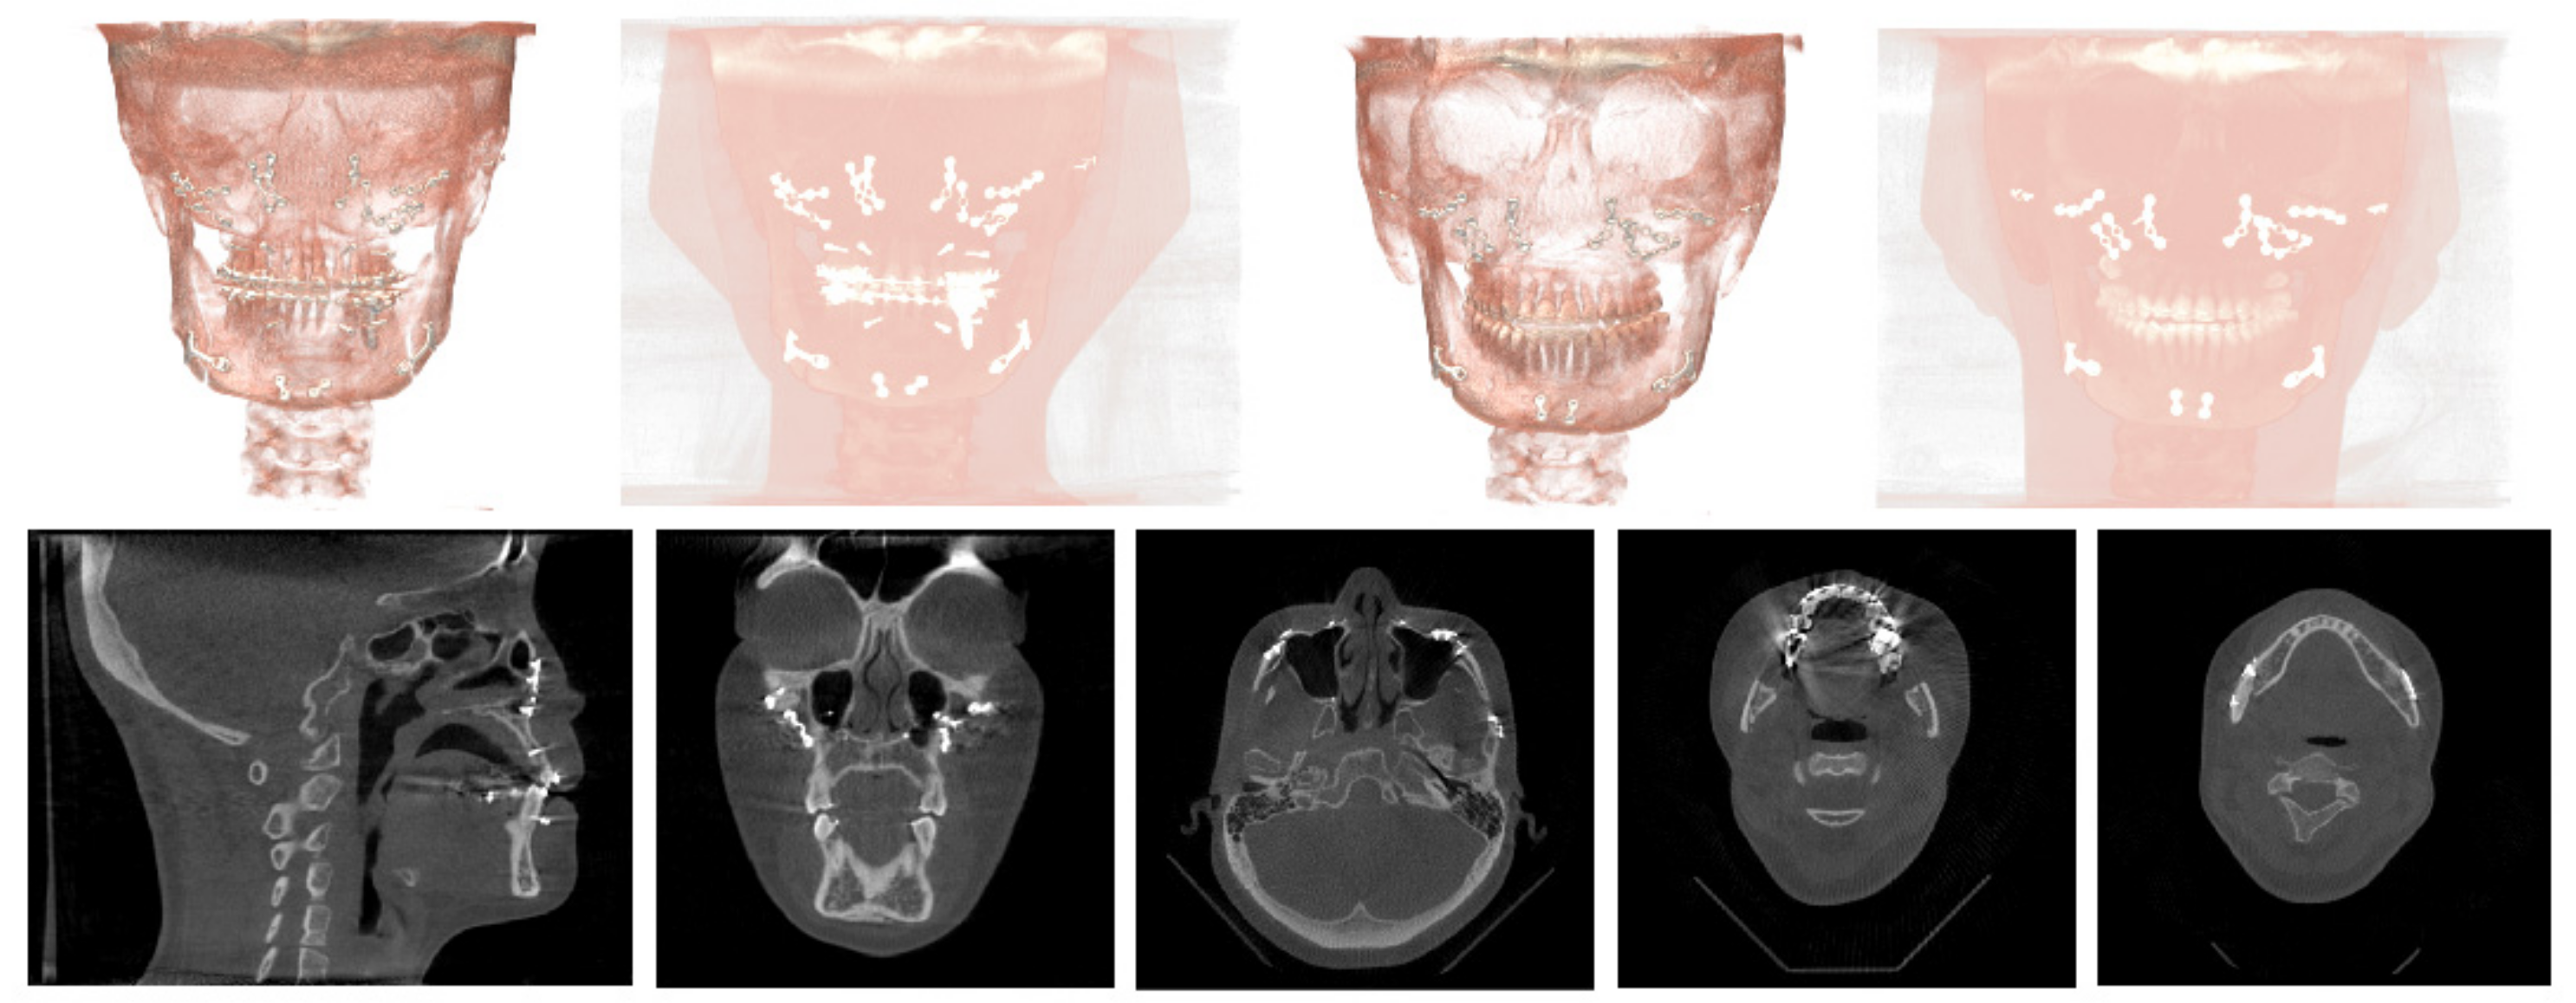

2.1. Data